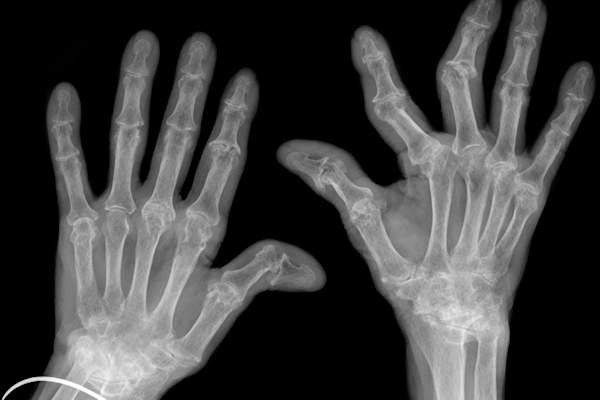

RA的手和脚开始,然后点击放大接头

风湿性关节炎最常发生于手或脚的小关节,后来扩展到较大的关节,如膝盖、脚踝、肘部、臀部、肩膀或颈部。在手上,RA可能会瞄准手腕或指节(底部和中间的指节,而不是顶部的关节)。在足部,它通常发生在连接脚和脚趾的关节处。与此同时,RA除了颈椎(颈部)外从不涉及脊柱,他补充道。风湿性关节炎的另一个特征是:它通常是对称的,影响身体两侧的同一个关节。

RA侵蚀骨骼

,细胞引起骨侵蚀宾厄姆博士说,RA,而另一方面,由破骨细胞的存在标示。严重的或未经治疗RA可引起骨骼磨损和关节移位,导致永久性畸形随着时间的推移。尽管如此,这通常仅发生在重度或未经处理的RA-并且可以通过早期诊断和恰当的治疗来防止。